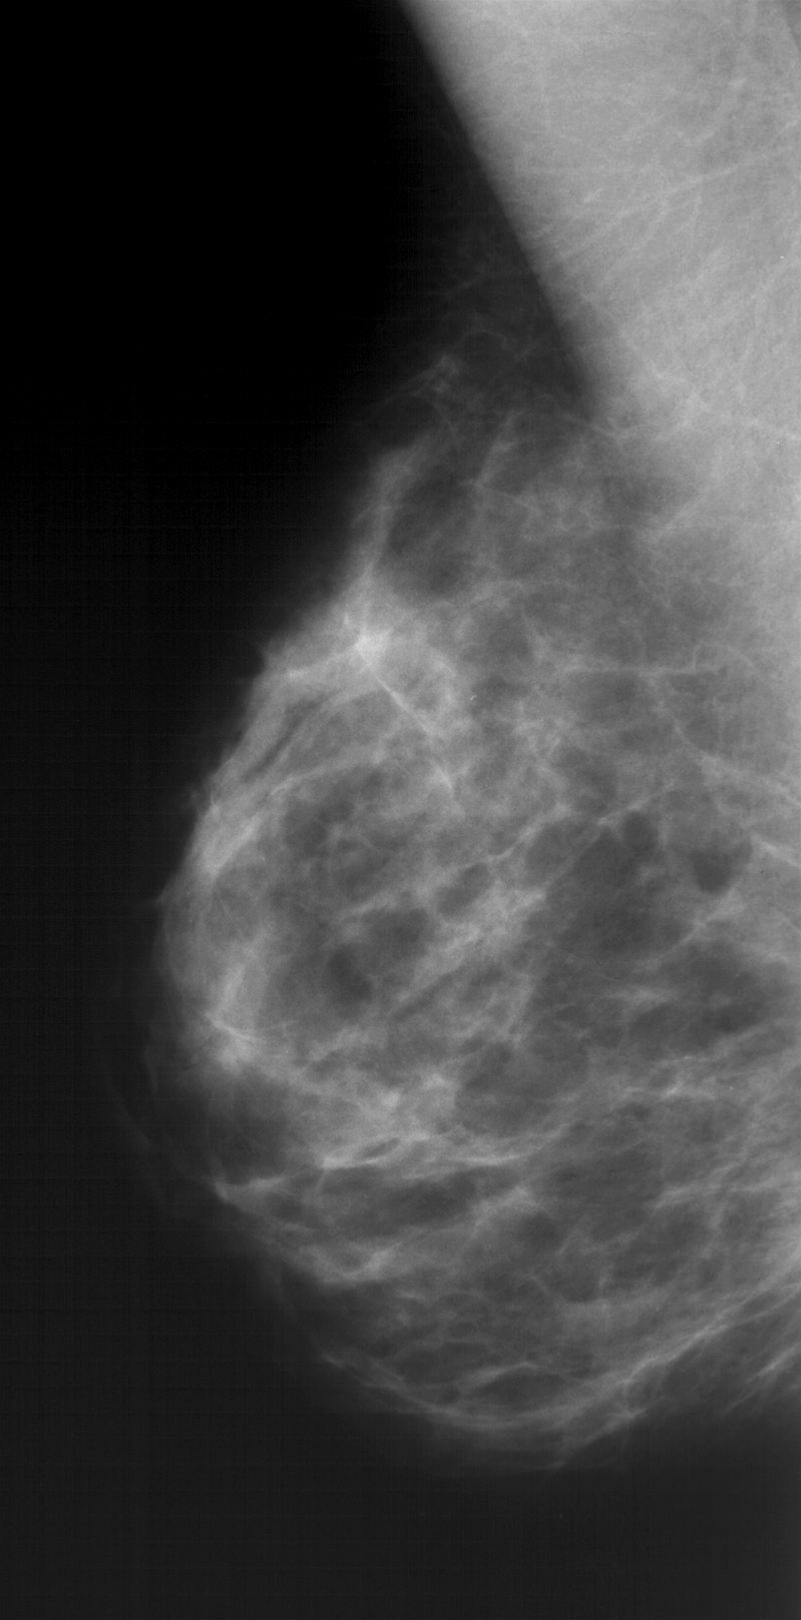

Bryst, Normal skråprojektion, Mammografi

Mammografiundersøgelse med skråprojektion. Normal undersøgelse.